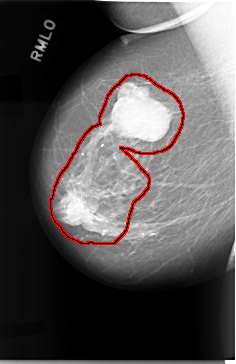

C_0019_1.RIGHT_MLO

FILE: C_0019_1.RIGHT_MLO.OVERLAY

TOTAL_ABNORMALITIES 1

ABNORMALITY 1

LESION_TYPE MASS SHAPE LOBULATED MARGINS CIRCUMSCRIBED

ASSESSMENT 5

SUBTLETY 5

PATHOLOGY MALIGNANT

TOTAL_OUTLINES 1

BOUNDARY